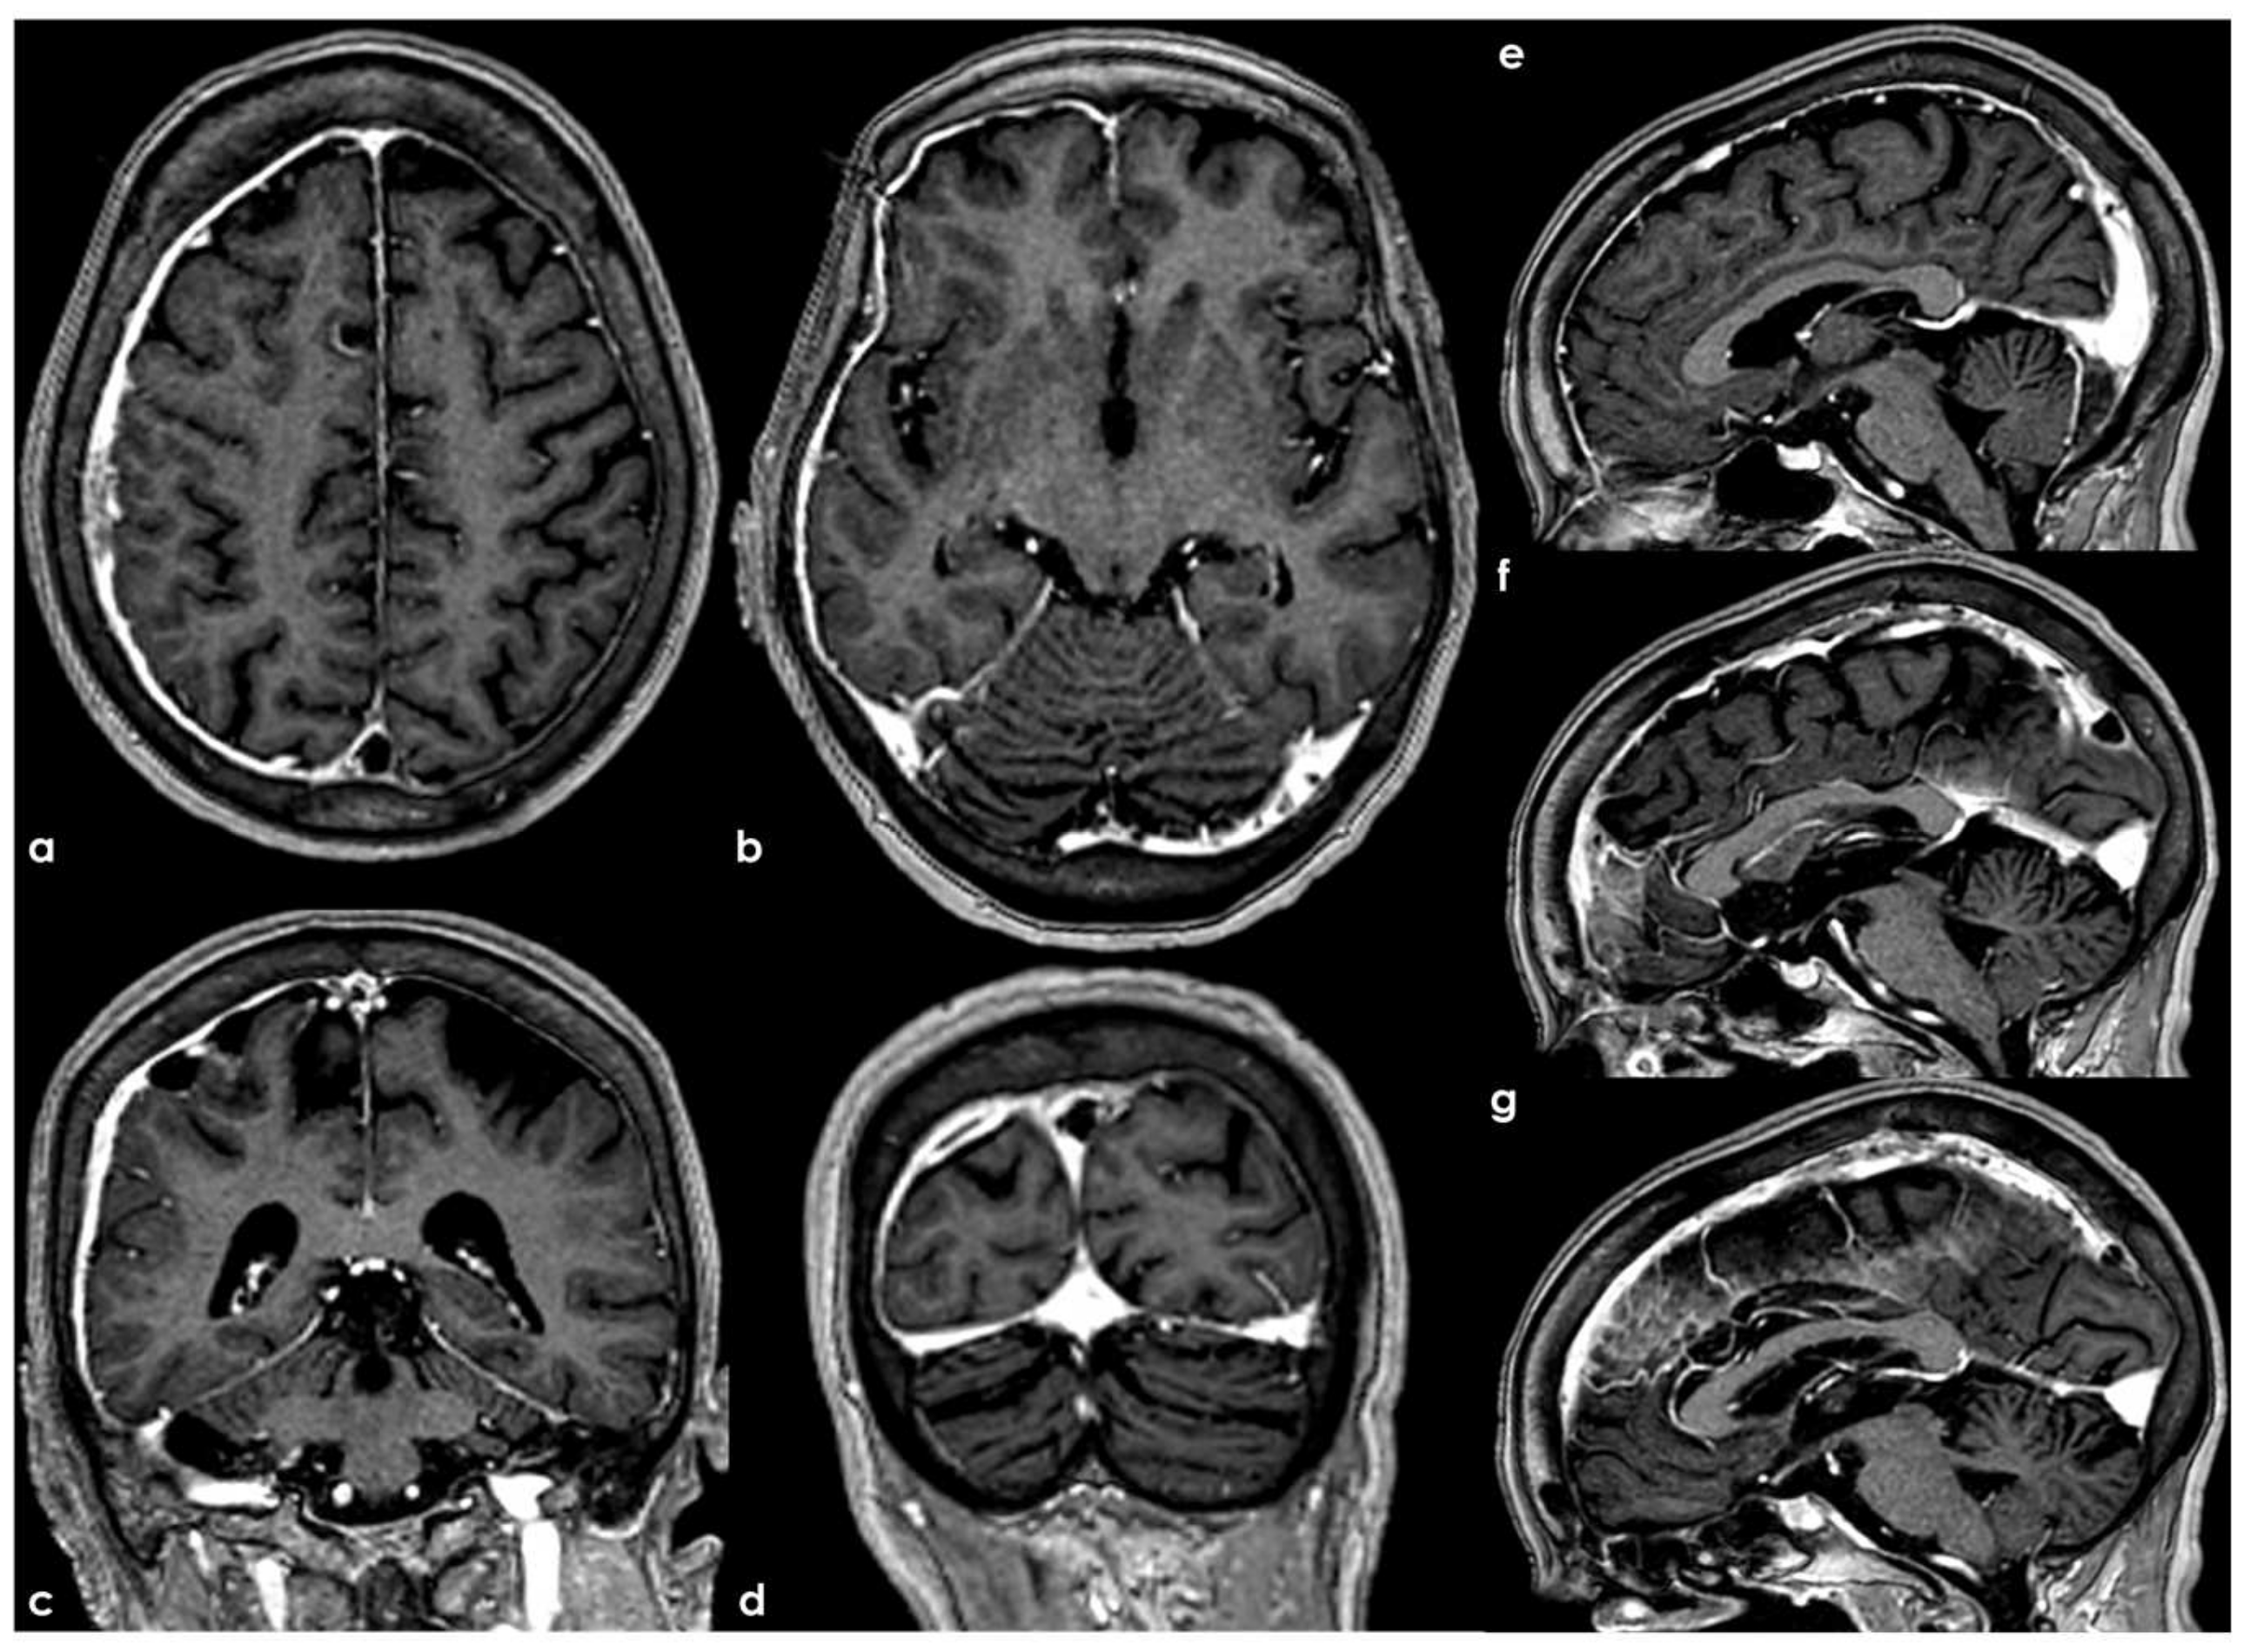

4.3.2. Transverse Sinus Variations

- Alper, F.; Kantarci, M.; Dane, S.; Gumustekin, K.; Onbas, O.; Durur, I. Importance of anatomical asymmetries of transverse sinuses: An MR venographic study. Cerebrovasc. Dis. 2004, 18, 236–239. [Google Scholar] [CrossRef] [PubMed]

- Fofi, L.; Giugni, E.; Vadalà, R.; Vanacore, N.; Aurilia, C.; Egeo, G.; Pierallini, A.; Barbanti, P. Cerebral transverse sinus morphology as detected by MR venography in patients with chronic migraine. Headache J. Head Face Pain 2012, 52, 1254–1261. [Google Scholar] [CrossRef]

- Han, K.; Chao, A.C.; Chang, F.C.; Hsu, H.Y.; Chung, C.P.; Sheng, W.Y.; Chan, L.; Wu, J.; Hu, H.H. Diagnosis of transverse sinus hypoplasia in magnetic resonance venography: New insights based on magnetic resonance imaging in combined dataset of venous outflow impairment case-control studies: Post hoc case-control study. Medicine 2016, 95, e2862. [Google Scholar] [CrossRef]

| Asymmetry and dominance | Asymmetry is a common feature, with the right TS typically larger and more dominant than the left. Right dominance: 59–62% of cases Left dominance: 25–30% of cases Codominance: 10–16% Hypoplasia or aplasia: Left hypoplasia: 39% of cases Left aplasia: 20% of individuals Right hypoplasia or aplasia: much rarer, affecting only 4–6% of cases. |

| Fibrous septa, bands, and doubling | Septa or fibrous bands can be present within the sinus, occasionally narrowing the lumen. Doubling of the TS has been observed, more commonly on the left. These structures may create flow gaps, often being mistaken for pathologies like venous thrombosis. |

| Connections and communications | The TS may have multiple openings connecting to the torcular Herophili. Rarely, an oblique sinus can connect the left and right TSs. Hypoplasia or aplasia of one TS often leads to compensatory enlargement of the contralateral sinus. In cases where the TS is absent, drainage is rerouted via the occipital sinus, marginal sinus, or superior petrosal sinus. |

| Developmental variations | Age-related changes: hypoplasia or aplasia may appear more frequently in older individuals due to changes in cranial venous flow. Overlapping lambdoidal sutures: in infants, these sutures may cause septation of the transverse sinus. Enlargement of structures: some individuals exhibit dilation of the distal TS, sigmoid sinus, or superior jugular bulb. |

| Rare and aberrant drainage patterns | Mastoid foramen drainage: Some cases show blood exiting the skull via the mastoid foramen rather than the jugular foramen. These cases may have an absent or hypoplastic sigmoid sinus. Alternative venous routes: The TS may connect with the cavernous sinus or ophthalmic veins via aberrant veins. |